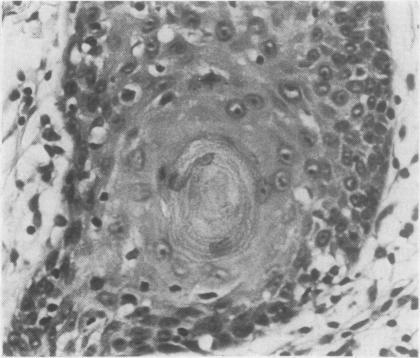

The pathological, cytological, and clinical features of vulvar intraepithelial neoplasia (VIN) are described. The rate of progression of VIN III to an invasive carcinoma is very low and spontaneous regression can occur. These features prevent the drawing of a direct analogy between vulvar and cervical intraepithelial neoplasia. The concept of microinvasive carcinoma of the vulva is discussed, and it is concluded that no satisfactory definition of this entity has been achieved.

本文描述了外阴上皮内瘤变(VIN)的病理、细胞学及临床特征。VIN III进展为浸润性癌的发生率很低,且可发生自发消退。这些特征使得外阴上皮内瘤变与宫颈上皮内瘤变无法直接进行类比。文中对外阴微浸润癌的概念进行了讨论,得出的结论是尚未对该实体达成令人满意的定义。